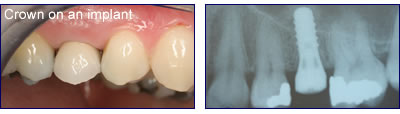

A dental implant is essentially an artificial tooth root which can support a crown, a bridge, or a denture. The implant is made of pure titanium which, for reasons still unknown today, will integrate (or osseointegrate) with the bone so that the implant and crown then act like a tooth. The technique avoids the need to wear a removable denture and feels part of the mouth as the original tooth used to do.

The implant is screw-shaped and is placed either into the socket of a recently-removed tooth or into a hole made within the bone by the surgeon. After a period of around six weeks the bone will have grown directly onto the surface of the implant-this is the fundamental process of Dental Implantology. The next stage is to attach a small cylinder to the top of the implant (called a healing abutment) to allow the gum to heal around this and then impressions are taken and a crown made to fit onto the top. The implant and crown thus resembles the root and crown of a natural tooth.